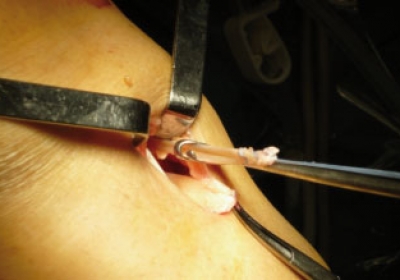

CIRUGÍA PROTÉSICA, MIS Y DE RECAMBIO

En aquellos casos en los que la articulación está deteriorada y los tratamientos conservadores no quirúrgicos no mejoran el dolor e incapacidad funcional del paciente es cuando está indicado un reemplazo articular.

Este reemplazo (artrosplatias) pueden ser unicompartimentales o totales según la extensión del desgate del cartílago, llegando a realizar miniartoplastias en aquellos casos en los que la zona a sustituir de la articulación es muy limitada.

La indicación de la prótesis se basa en el grado de afectación , limitación funcional y el dolor; y secundariamente en la edad, por lo que en ocasiones, puede ser necesaria una cirugía protésica en gente joven, como por ejemplo en la artritis reumatoide juvenil o en lesiones post.traumaticas graves. En estas ocasiones es recomendable utilizar diseños que aseguren la máxima durabilidad del implante como es el caso de las prótesis rotatorias o de platillos móviles u otros como el de la Protesis Advance Medial Pivot (Wrigth), que imita la funcionabilidad de la rodilla humana.¿Qué es la cirugía MIS (Minimal Invasive Surgery)?

Este tipo de cirugía consiste en practicar la implantación de prótesis mediante incisiones muy pequeñas que respetan al máximo las partes blandas. De esta forma, conseguimos acelerar la recuperación y reducir el tiempo en la clínica del paciente, que sólo está unos pocos días. Siempre en aquellos casos en los que este indicado. Siempre valorando cada caso en particular para poder garantizar los mejores resultados y sin olvidar el principal objetivo: asegurar un resultado que perdure en el tiempo.Sustitución de prótesis: recambios y revisiones